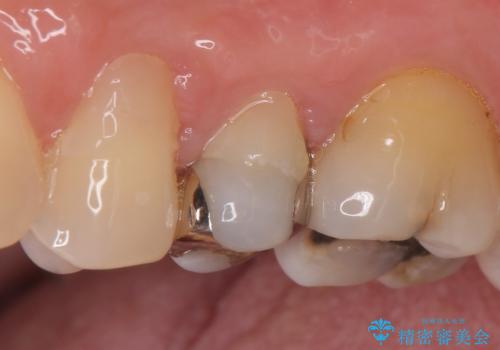

- 左上5番目の歯がしみるといらっしゃった方の症例です。

頬側の樹脂及び銀歯を除去後、オールセラミッククラウンにて補綴を行いました。